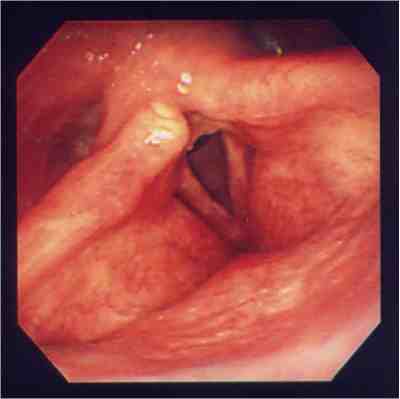

手術前の声帯手術後の声帯

気道が広くなっているのがわかります。